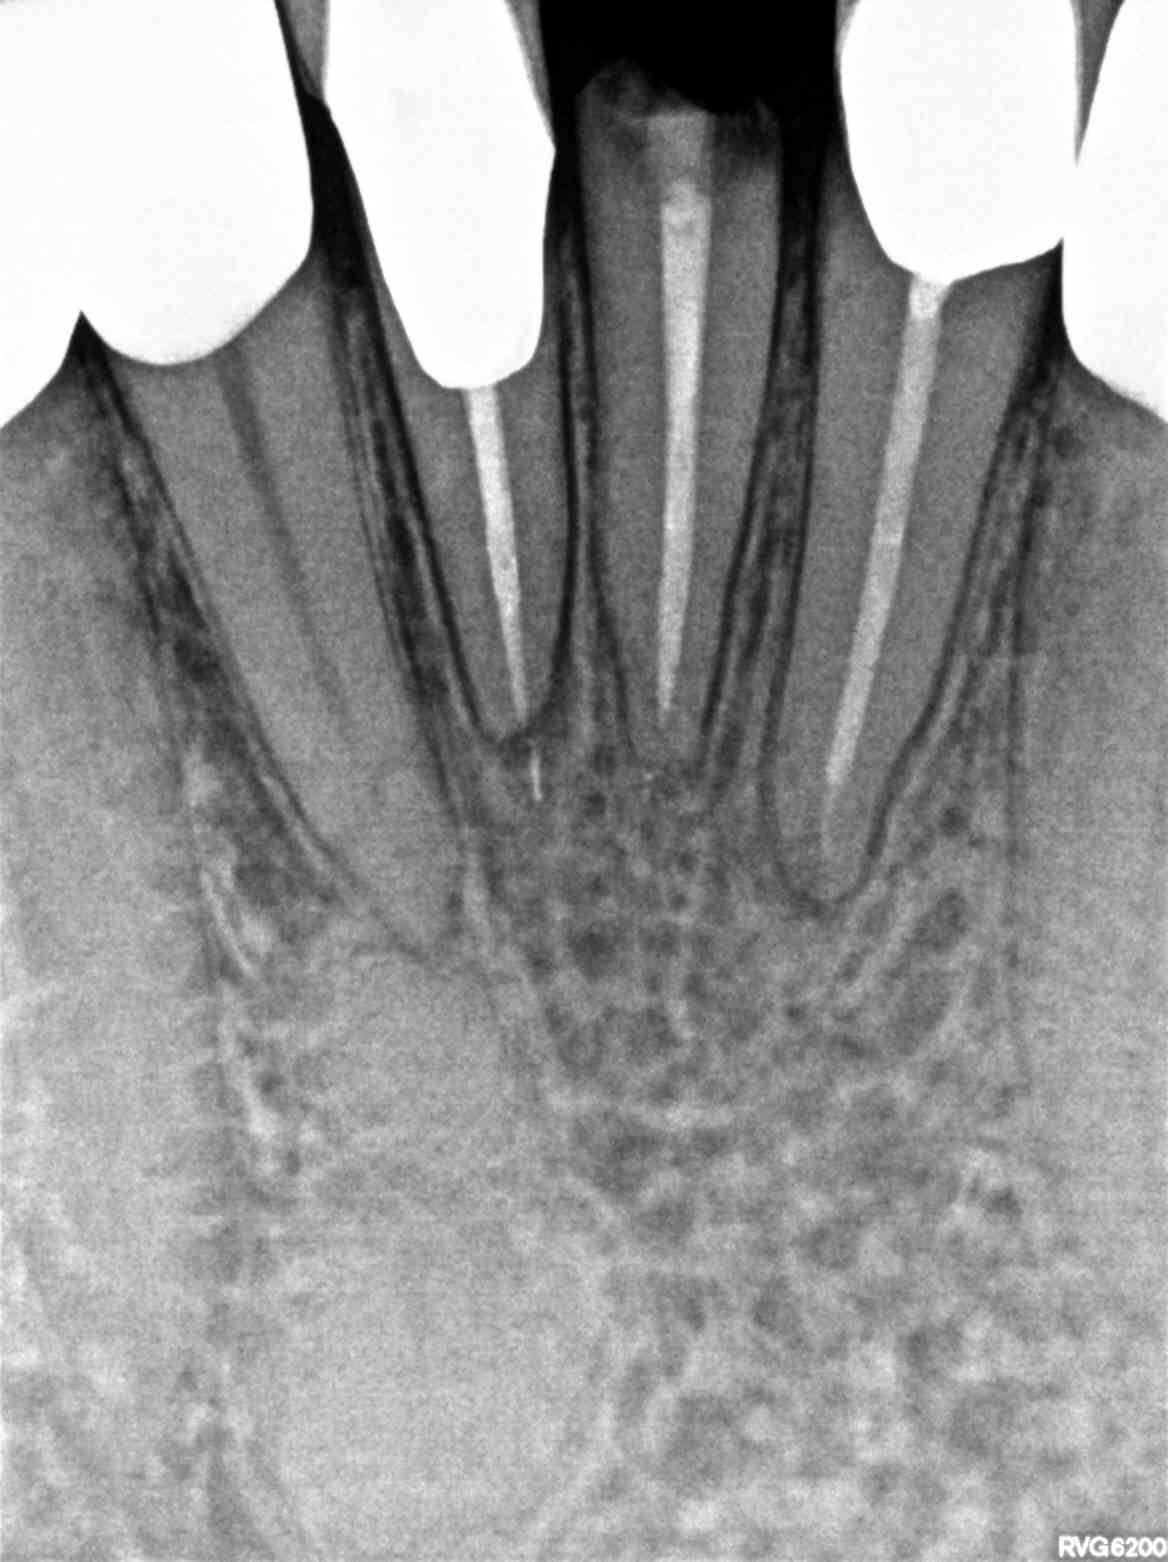

Dental Auction No. 10390: Extract, implant, abutment, implant crown #24, Post/core & crown #6 & 12

#6 & 12 post/core & crown, #24 Extract, bone graft, implant, abutment & implant crown

Auction images